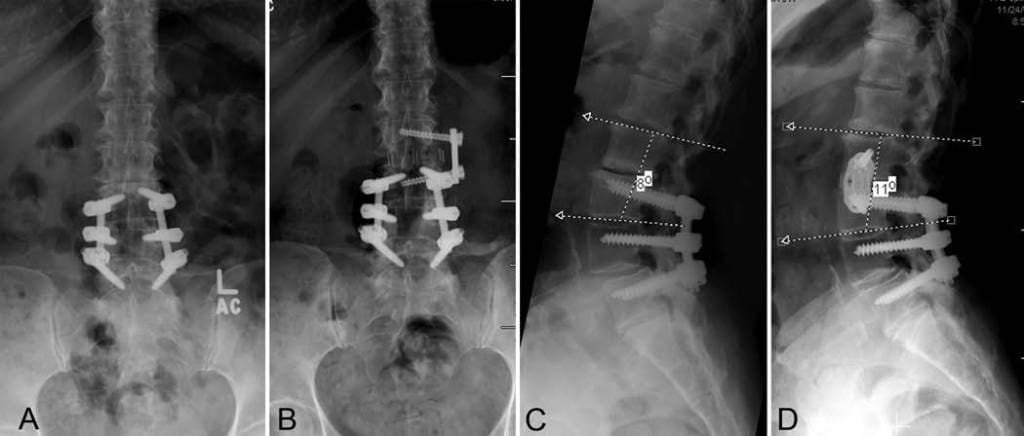

J Neurosurg Spine 21:861–866, 2014 Adjacent-segment degeneration and stenosis are common in patients who have undergone previous lumbar fusion.